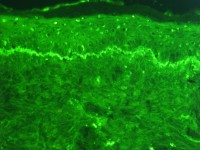

![Immunofluorescentie microscopie (IF) (click on photo to enlarge) [source: Krzysztof Blachnicki - Wikimedia - Creative Commons License 1.0 - Public Domain Image] Immunofluorescentie microscopie (IF)](../../../images/figures/immunofluorescentie-techniek-1z.jpg) |

| IF microscopie |

IF microscoop |

lupusband |

Foto lupusband:

Emmanuelm - Wikipedia (Creative Commons License

3.0).

De techniek van de directe IF werd ontwikkeld in 1963 door Burnham, die

aantoonde dat er in de huidafwijkingen bij SLE patiënten diverse verschillende

immunoglobulinen en complementfactoren aanwezing zijn langs de

basale

membraan; hij introduceerde ook het begrip

lupusband.